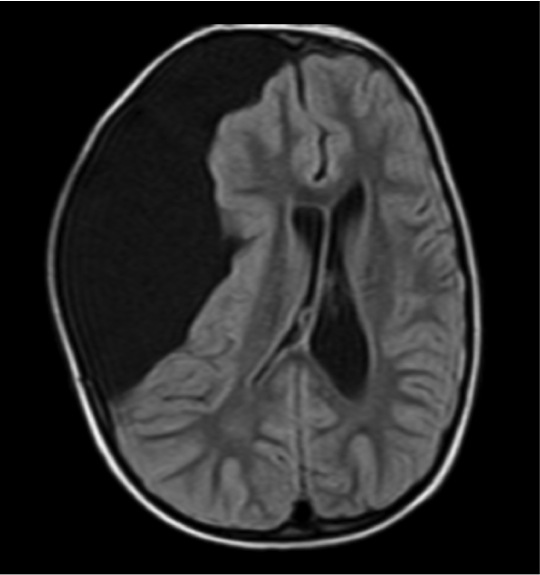

¿Qué primera prueba complementaria solicitaría?